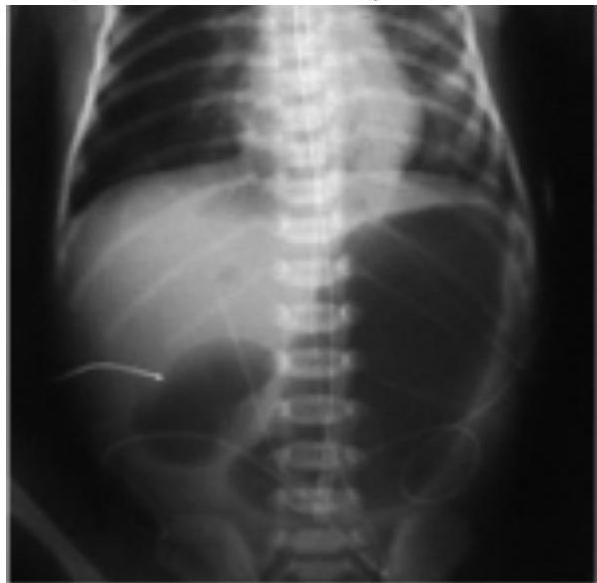

Duodenal Atresia

X-Ray Finding:

- Double bubble sign (should not see gas beyond the double bubbles)

- 1 bubble in stomach, 1 in 1st part of duodenum

Associated with:

- Down syndrome

Management:

- Duodenostomy

Hirschsprung Disease

describe x-ray

There is fecal impaction, transitional zone (dilated part proximally and constricted part distally)

Barium Enema Findings:

- Fecal impaction

- Transitional zone (dilated part proximally, constricted part distally)

- Narrow distal segment

- Dilated proximal segment

- Funnel-shaped dilatation at level of transitional zone

Causes:

- Absence of ganglion cells (aganglionic megacolon)

Presentations:

- Delayed passage of meconium

- Chronic constipation

- Toxic megacolon

- Signs of intestinal obstruction

Confirmation:

- Rectal biopsy

- Resuscitation, NPO and IV fluids

- Antibiotics

- Rectal tube, irrigation

- At age 6-12 months: resection of aganglionic segment and anastomosing (formal pull-through procedure)